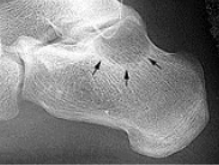

| What do the arrows show? | Stress fracture |